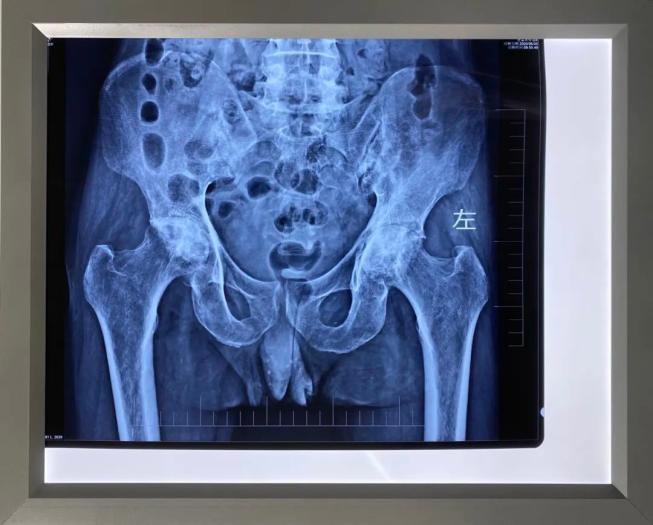

2020年06月10日,我院外科成功为一位53岁贫困户大叔实施右侧人工全髋关节置换术。受尽病魔困扰的大叔终于摆脱轮椅能站立行走,近日即将出院。

今年6月,在驻村扶贫工作队人员指引下,来到我院外科就诊,外科主任胡柱主治医师仔细评估患者病情及经济情况后予收治入院。经过术前准备、术后护理及存在的风险情况的充分评估,制定了最佳的手术治疗方案,在来宾市人民医院专家的协助下,成功地为患者施行了右侧人工全髋关节置换术。

在医疗费用上按政府健康扶贫兜底政策给予了最大程度照顾。经主治医师韦正果医师介绍:根据病情评估,预计三个月后再行左侧人工全髋关节置换术,此后患者就可真正摆脱生活不能自理、长期需要人照顾的困境。